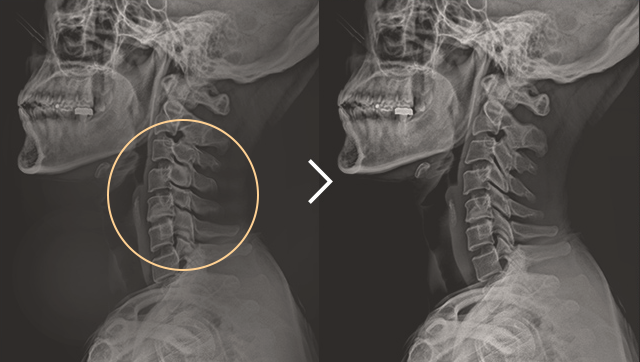

• 일자목 치료 전후사진

일자목 증후군 2개월 감압 치료 후

정상 소견으로 회복됨